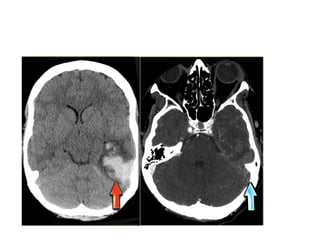

PICA Infarction

Sharp midline delineation

4.Dense MCA sign

• This is a result of thrombus or embolus in

Hemorrhagic infarcts

15% of MCA infarcts are initially hemorrhagic.